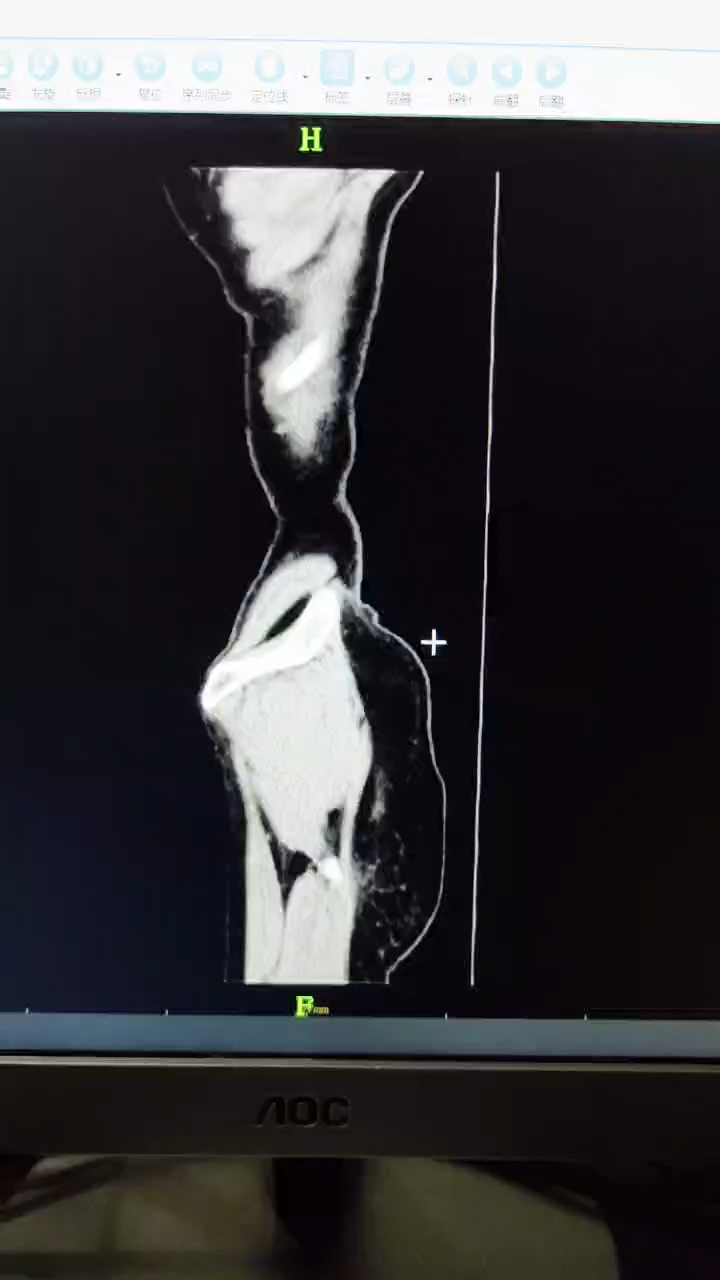

辅助检查:腹部B超提示上腹部不规则低回声包块,腹部CT检查提示腹腔多发占位性病变,考虑良性可能(如下图所示)。

冠状位

矢状位

临床诊断:腹腔多发占位性病变性质待查。